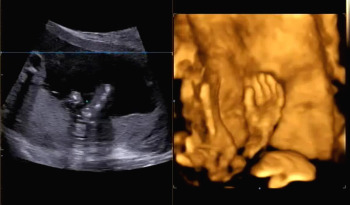

입체 초음파 또한 복부초음파처럼 침대에 누워 태아의 상태를 확인하는데 정밀검사처럼 태아의 손, 발뿐 아니라 얼굴 생김새까지 확인이 가능하다.

바른 자세로 누워 초음파를 시작했다. 손가락, 발가락뿐 아니라 양측 귀까지 입체 초음파를 통해 확인하고 태아의 얼굴 생김새를 확인했다. 일반 초음파로 확인할 때와 다르게 입체적으로 보이는 태아의 모습에 신기했다.

다른 부분을 확인하고 태아의 얼굴을 보기 위해 초음파를 시작하는데 아기가 자궁벽을 향해 얼굴을 붙이고 있어서 초음파에서 얼굴을 보기 힘들었다. 입체 초음파로 생김새를 정확히 보기 위해서는 태아가 양수가 많이 있는 방향으로 얼굴을 가리지 않아야 한다. 햇님이는 벽에 얼굴을 붙인 것뿐 아니라 손으로 얼굴을 가려서 더욱 보기가 힘들었다. 사실 입체 초음파를 보기 전 일반 초음파를 확인할 때 얼굴을 보기 힘들었어서 이번에도 어려울 거라고 예상은 했었다. 그래서 초음파를 확인하는 선생님이 나의 배를 열심히 흔들었다. 태아가 양수의 흔들림에 자세를 바꾸기를 바라며 나의 배를 흔들고 눌렀는데 초음파에서 얼굴 정면을 볼 수 없었다.

복부를 흔들고 누른다고 엄마인 나까지 배가 아팠는데 괜히 얼굴 한번 보겠다고 태아에게까지 스트레스를 준 것은 아닌가 걱정했다. 평소 태동이 격렬했던 햇님이가 걱정되는 마음 탓에 태동이 줄어든 것 같아 초음파를 시행한 당일에 열심히 태담을 했다. 만약 내가 또 임신을 하게 된다면 입체 초음파를 시행하지 말아야겠다고 생각했다.